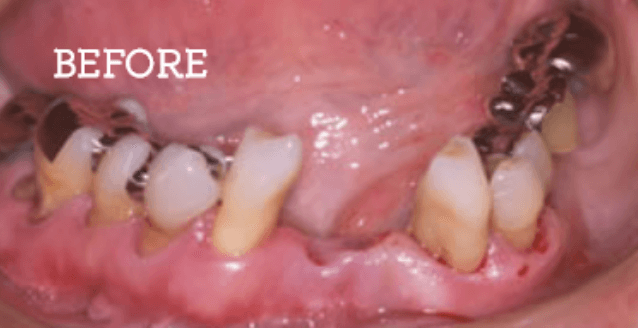

お困りごとを参考に、治療のbefore・afterが確認できます。治療過程や期間、費用などを参考にご覧ください。